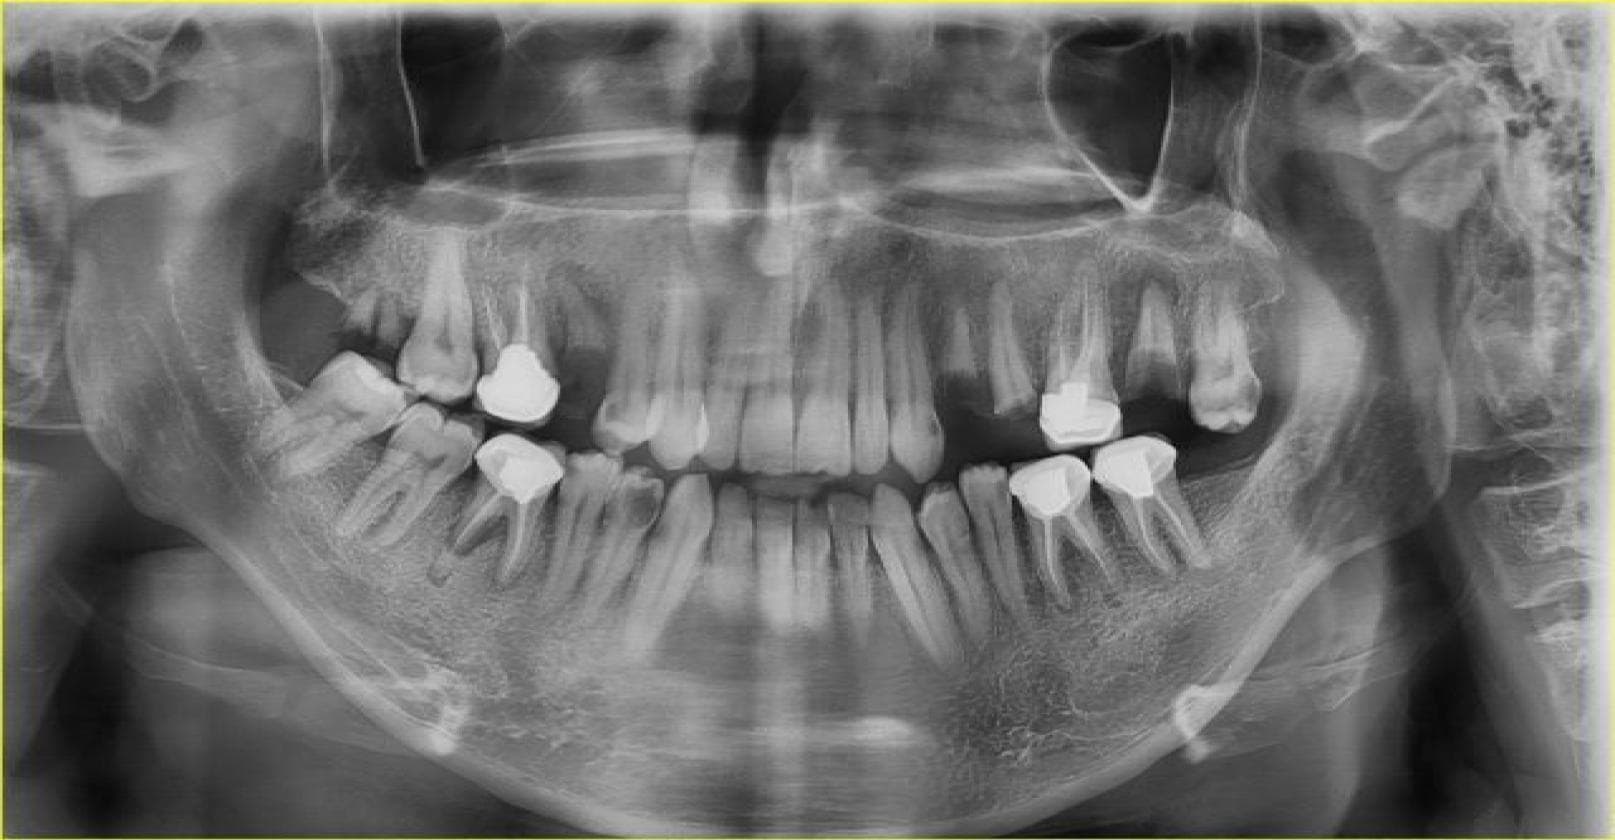

1. Upload do Exame

Envie radiografias panorâmicas ou periapicais através de nossa plataforma segura e criptografada (HIPAA/LGPD).

2. Análise via IA

Nossos modelos de visão computacional processam a imagem, identificando patologias e anatomia em tempo real.

Anatomia & Dentes

Numeração automática (FDI/Universal), reconhecimento de coroas, implantes e dentes ausentes.